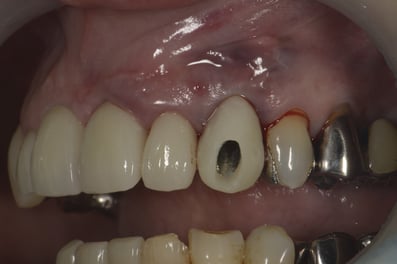

抜歯した直後にインプラントを埋入し、仮の歯を作製、唇側の骨のボリュームを保つために人工骨と結合組織を同時に移植する非常に優れた方法です。

既存の骨の形態分類(ClassⅠ〜Ⅳ)のClassⅢまでは埋入可能とされています。